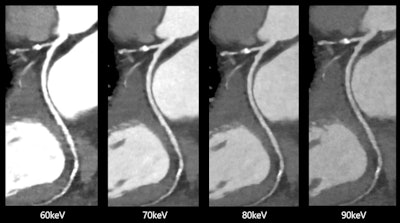

Spectral cardiovascular images produced by Canon Medical Systems' Aquilion One/Prism Edition CT with FDA-cleared deep learning software. Images courtesy of Canon Medical Systems.

Spectral cardiovascular images produced by Canon Medical Systems' Aquilion One/Prism Edition CT with FDA-cleared deep learning software. Images courtesy of Canon Medical Systems.The clearance makes it possible for Canon to market the scanner for use in acquiring 0.275-second whole-heart images in one heartbeat, with rapid kVp switching and deep-learning reconstruction of spectral CT images.